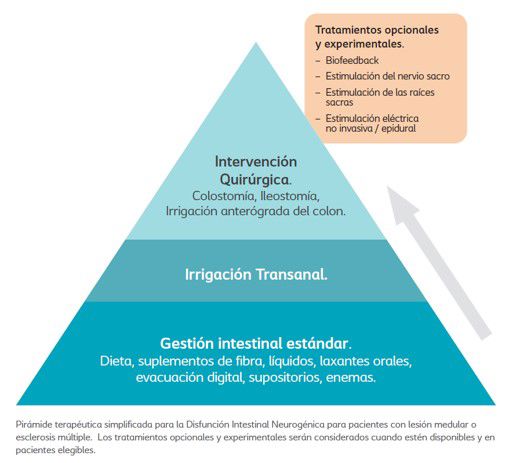

La ITA como opción de tratamiento

En 2013, una revisión de consenso internacional llevada a cabo por 12 especialistas de diversas disciplinas, con experiencia en la prescripción y el seguimiento de pacientes que utilizaban la ITA, elaboró una pirámide de tratamiento para gestionar la Disfunción Intestinal Neurogénica6. Este algoritmo de tratamiento presentado en forma de pirámide, no se correspondía completamente con la práctica clínica real, conteniendo tanto tratamientos aún en fase experimental como tratamientos que no estaban disponibles en todos los centros. Por lo tanto, era necesario un algoritmo de tratamiento actualizado. En 2023 se publicó en Journal of Clinical Medicine un nuevo artículo, en el que los autores proponen una versión simplificada de la pirámide de tratamiento, con el objetivo de guiar a los clínicos en el

tratamiento de la Disfunción Intestinal Neurogénica.